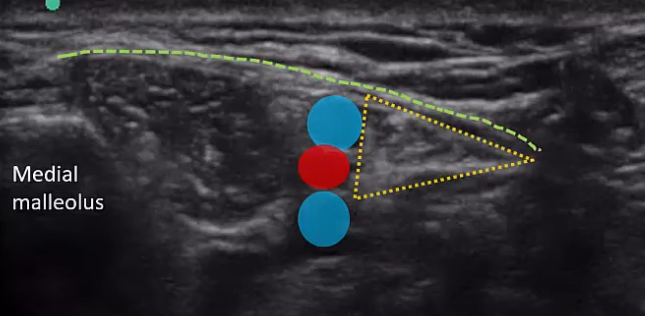

Tibial n.

larger terminal branch of sciatic n.

running in tarsal tunnel